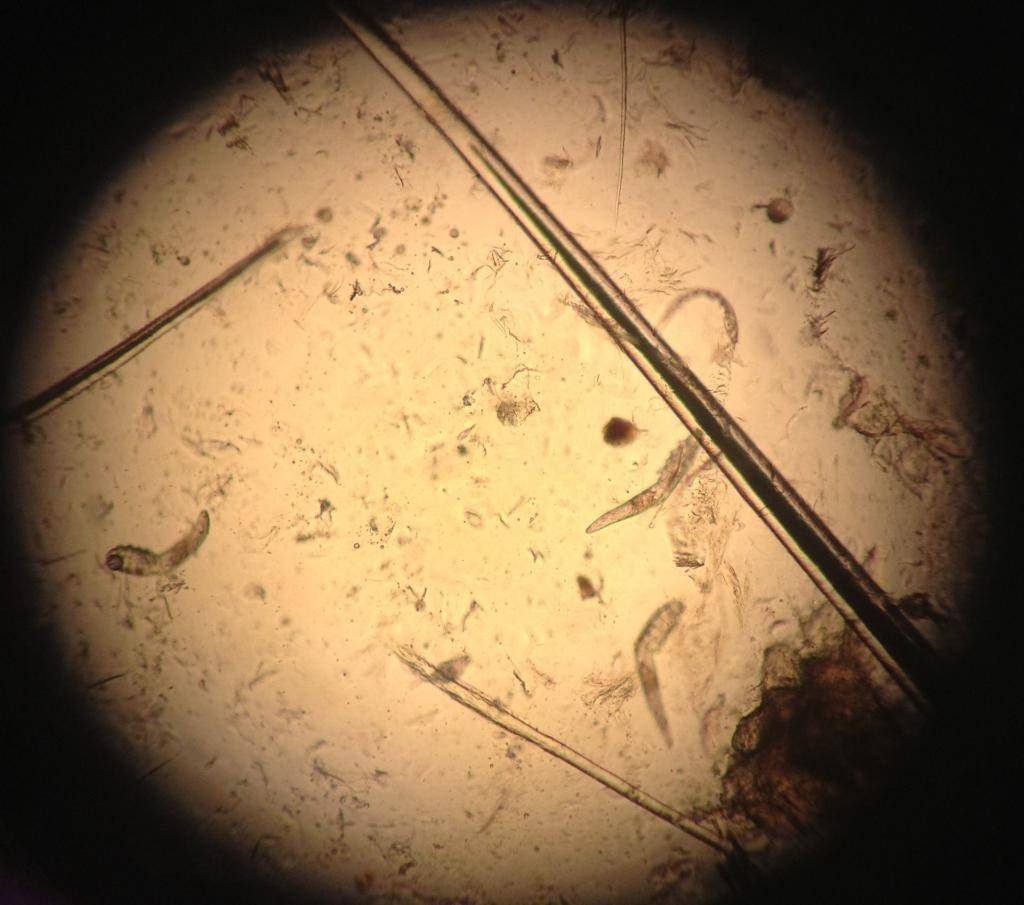

Жизненный цикл клеща составляет примерно 15-25 дней, в течение которых демодекс питается отмершими клетками кожи и секретом сальных желез.

Размножается демодекс путем откладывания яиц, из которых очень скоро появляются личинки. Взрослый клещ после яйцекладки умирает в фолликуле или сальной железе. Через 60 часов появляются неподвижные личинки, которые объедаются жиром или клетками эпидермиса на протяжении 40 часов и превращаются в нимфу-1 или протонимфу, у которой есть уже голова, но она ещё неподвижна.

Проходит 72 часа и на кожных покровах начинает передвигаться нимфа-2 или дейтонимфа со сформированным хвостом. Опять через 60 часов нимфа-2 превращается в половозрелую особь, которая откладывает яйца и умирает, становясь пищей для вновь вылупившихся личинок, нимф и молодых особей клеща. Это при нормальном протекании процесса, который по статистике наблюдается в 90% населения и лишь в 10% людей клещ начинает патологически размножаться.